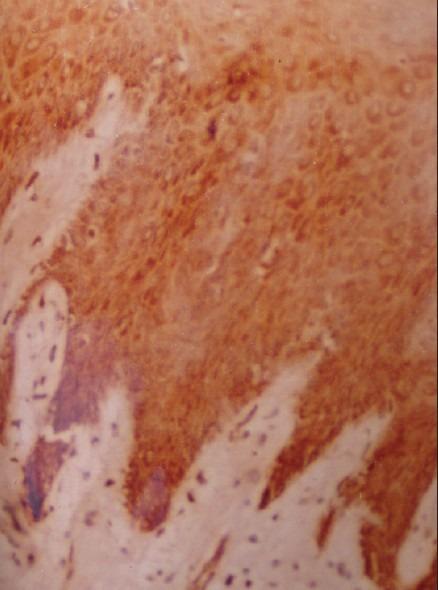

The aim of the study was to assess the expression of epithelial growth factor receptor (EGFR) in normal oral mucosa and varying grades of oral epithelial dysplasia (OED) and to correlate these findings, with clinicopathologic features and findings on routine hematoxylin and eosin-stained (H and E) sections.

Twenty-nine formalin-fixed, paraffin-embedded blocks of various grades of OED and 10 normal mucosa were stained with routine H and E and immunostained with EGFR by avidin-biotin method.

The results showed a significant increase in the staining reactions in varying grades of dysplasia as compared with normal mucosa.